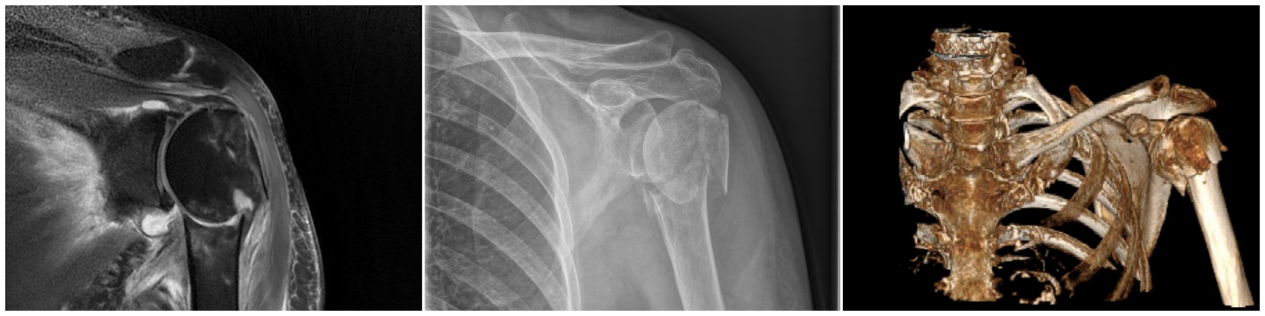

2025年2月4日,正是蛇年春节假期的最后一天。一位74岁高龄的患者杨女士在家人的陪伴下前来医院创伤骨科(骨一科)寻求救治。据了解,杨女士在行走时不慎摔伤,左肩部受伤并出现剧烈疼痛。创伤骨科(骨一科)医生立即为患者完善放射检查,发现患者左侧肱骨近端骨折,骨折块粉碎为四部分,且肱骨头严重塌陷移位。另外,患者伴有骨质疏松。若采用传统手术,对骨折位置进行切开复位钢板螺钉内固定术,不仅患者愈后效果不佳,且易出现肱骨头坏死和肩周粘连等并发症。术后患者肩关节功能恢复不理想,将会严重影响生活质量。如何让患者获得最佳的治疗方案,创伤更小、更好地恢复肩关节功能?成为创伤骨科(骨一科)医疗团队讨论的焦点。

▲术前检查